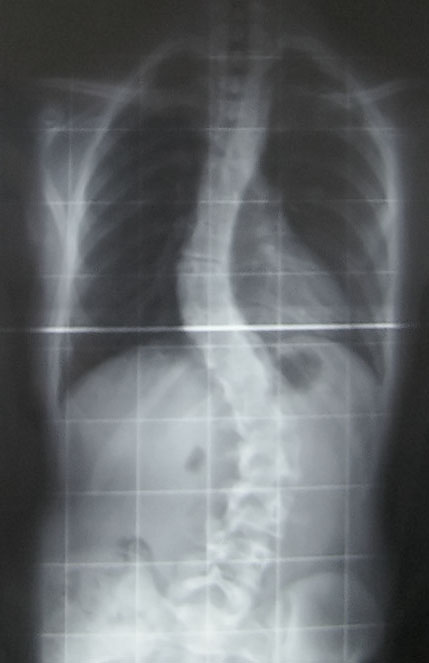

For individuals with scoliosis, many often ask the question is there anything that can be done? And the answer is “it depends”…but probably yes.

Many factors go in to answering the question of what can be done to help someone with scoliosis. Things like strength, flexibility, degree of curve, current activity level and more go into determining what is possible.